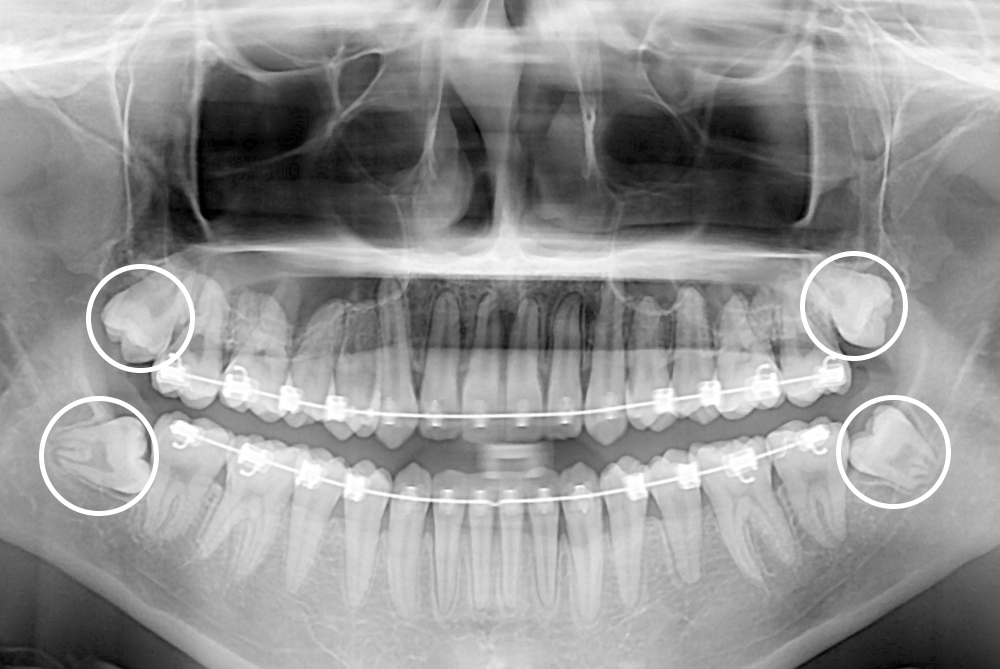

[사랑니] 매복 사랑니 발치

치료전 : 2017-04-07

세종치과는 구강악안면외과학 박사이신 원장님이 발치하는 치과입니다.